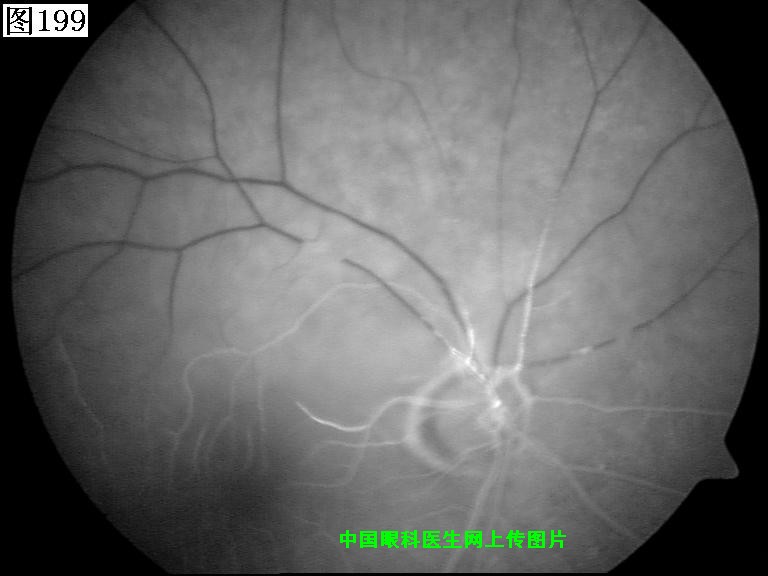

197 198 199 200